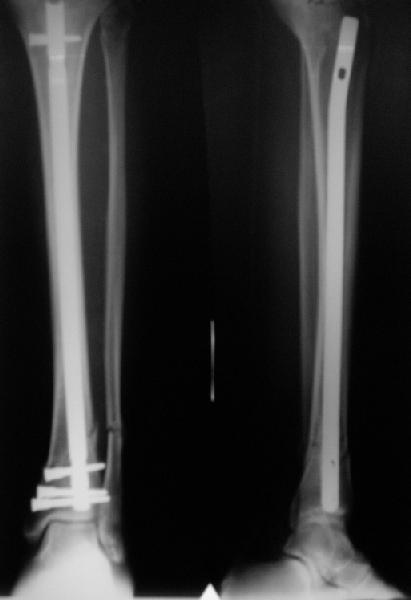

Направили к нам пациентку 35 лет с переломом дистального отдела костей голени.

У нас сделали снимок сзахватом обоих суставов - еще и проксимальный метафиз сломан. Чем бы у вас фиксировали такой перелом? Как его правильно закодировать по классификации АО?

Можно либо как два перелома - 41A+42B. А можно как один сегментарный 42С.